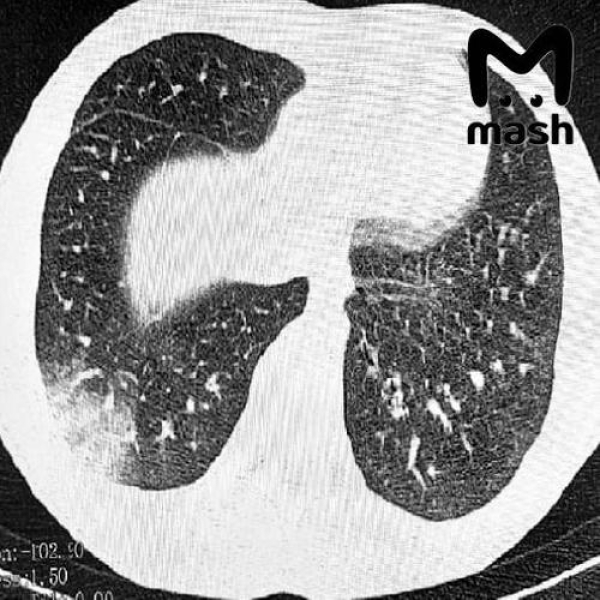

У 16-летнего пациента — серьёзная дыхательная недостаточность, потребовалась искусственная вентиляция лёгких. У другого — двусторонняя вейп-ассоциированная пневмония EVALI, врачи сделали операцию. Похожие случаи фиксируют и в других регионах России: первые в Москве в 2021-м, затем в Томске, где в прошлом году пострадали двое несовершеннолетних.

Врачи говорят: электронки серьёзно портят здоровье. Жидкости в дуделках содержат химические вещества, которые повреждают дыхательные пути, вызывают воспаление лёгких и приводят к проблемам с дыханием.